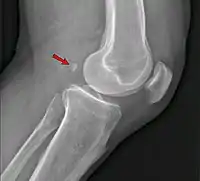

Fabela, no contexto da medicina, é um osso sesamoide situado na cabeça lateral do músculo gastrocnêmio nos membros inferiores, logo atrás da articulação do joelho.[1]

A sua função ainda é um mistério para a ciência. Já sua importância se deve, principalmente, por este ser bastante confundido com um fragmento ósseo ou um corpo estranho em radiografias da área. Segundo o pesquisador Michael Berthaume, do departamento de bioengenharia do Imperial College de Londres, "a fabela pode se comportar como outros ossos sesamoides, ajudando a reduzir o atrito nos tendões e redirecionando as forças dos músculos ou, como no caso da rótula, aumentando a força mecânica do músculo".[2]

A fabela localiza-se no tendão da cabeça lateral do músculo gastrocnêmio e aparece circundada em seu aspecto anterior e posterior pelas fibras tendíneas nos estudos histológicos. Está ligado na maioria dos casos à cabeça da fíbula por um ligamento fabelo-fibular. Seu tamanho é variável, entre 4 e 13 mm.